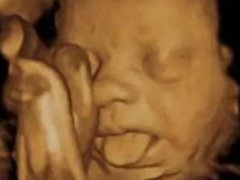

胎宝宝竟在妈妈肚子里做这么多事

前几天我随手翻了翻以前的朋友圈,看到mini包第一次打嗝,第一次胎动,还有四维照片里扮鬼脸的小模样,嘴角就不自觉上扬! 其实孩子还是胎宝宝时,就已经开始各种“搞怪”了,这...

四维彩超那么贵不懂这些就白做了

无论你现在是否已经怀孕了,产检的重要性都是知道。前几天我给大家分享了如何看懂尿检单和血检单。是不是还有一个一个关键的产检报告单还没有和大家分享呢?那就是四维彩超的报...